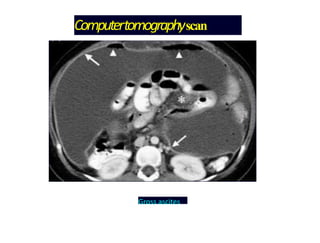

Computertomographyscan

Gross ascites